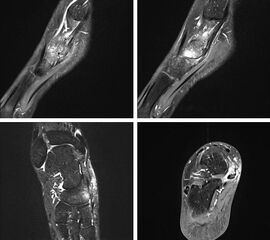

- Bei unklarem Befund kann die Bildgebung mittels MRTvervollständigt werden. Das MRT zeigt eine mögliche Aktivierung der Synchondrose bzw. erlaubt auch andere Differentialdiagnosen (Tendonose der Tibialis posterior Sehne, Verletzung Deltaband, Verletzung Pfannenband) auszuschließen (Abb. 3) 6 (Szeimies 2014).